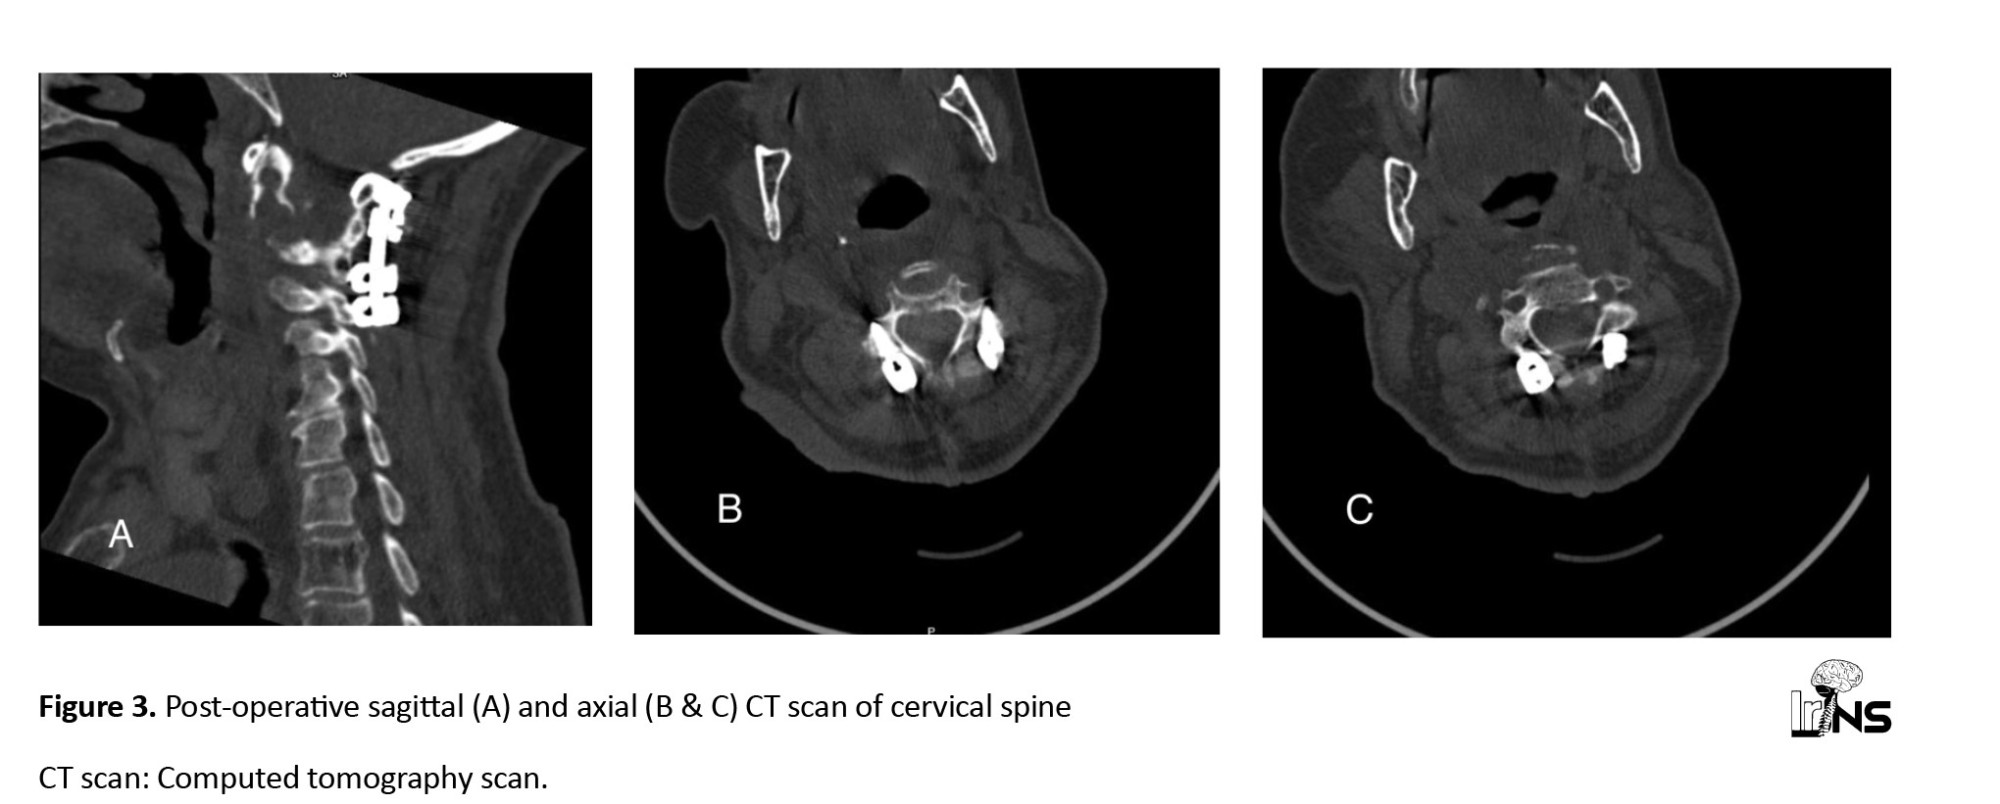

Given the symptoms, patient age, and structural instability of the craniospinal junction with the lytic C2 lesion, we decided to perform posterior cervical fusion with three main objectives: To improve the clinical symptoms, stabilize the cervical spine, and prevent devastating neurological consequences. Surgery was performed under general anesthesia and neurophysiological monitoring. The patient was premedicated with intravenous antibiotics (2 g of sodium cefazolin). The patient was placed in the prone position with an adequate cushion, and his head was fixed using a Mayfield clamp under general anesthesia. After division of the skin and posterior neck muscles, the Laminar hook on the C1 and C3-C4 lateral mass was inserted. An additional posterior transpedicular biopsy of the bone marrow was performed using the Jamshidi needle. Within 1 d postoperatively, the patient’s pain resolved without new neurological deficits, and a CT scan confirmed cervical stability (

Figure 3).

Moreover, the fragile outer borders of the C2 body pose a significant fracture risk, with potentially catastrophic consequences. Single-session posterior cervical fixation is rarely recommended for treating metastatic cervical instability. To our knowledge, the transpedicular approach to access the C2 body is not a safe option due to the vertebral arteries’ proximity and the axis pedicles’ small size [3]. The transoral approach provides the most straightforward access, offering the advantage of a short distance to the C2 vertebral body, thereby minimizing the risk of injury to crucial vascular structures [13, 14]. However, we decided against a second surgery with a higher risk of infection and bleeding due to the undiagnosed nature of the lesion. Therefore, posterior transpedicular biopsy via a Jamshidi needle was the optimal option for confirming the diagnosis of SBP. The posterior approach also allowed stabilization of the craniocervical junction. After careful consideration, the posterior approach was selected, and C1 laminar hooks with C3-C4 lateral mass fixation were performed along with C2 transpedicular biopsy.

Several authors have recommended injecting selective bone cement to prevent vertebral collapse [2, 3, 5, 15]. However, we considered our patient a high-risk case for cement injection due to the thinness of the vertebral borders, which could easily be disrupted, potentially leading to catastrophic neurological consequences. Cervical fixation significantly improves the patient’s quality of life. Our patient experienced a reduction in cervical pain 7 days after surgery and was able to ambulate without a soft neck collar.